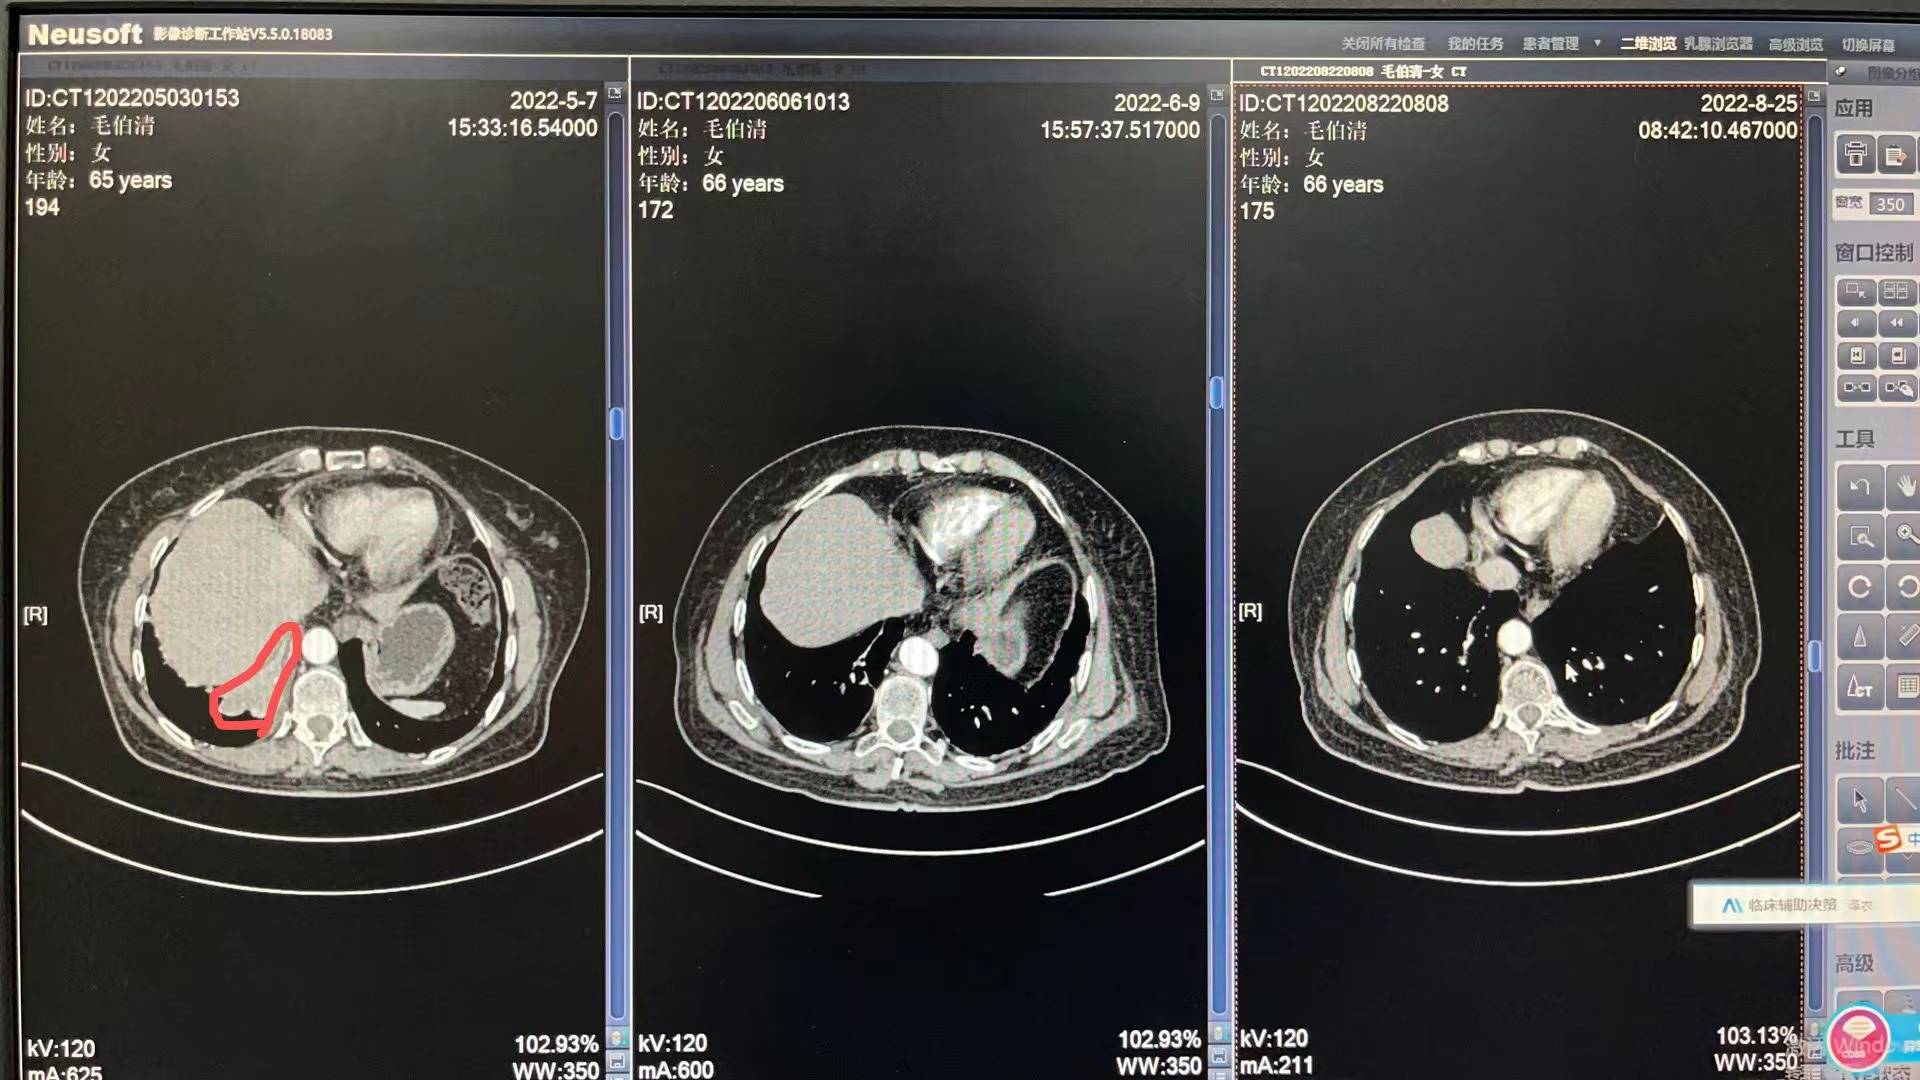

5月3号妈妈入院开始各种检查流程,5月13号病理出来,没有逃过此劫,确诊小细胞肺癌T4N2M0 IIIc期 局限期。妈妈的肿瘤是比较大的,5月14号上治疗,依托铂苷+顺铂,第二次化疗是6月6号,第三次化疗是6月29号,都是化疗三天出院,打升白针,便秘严重,喝乳果糖没啥用,两三天后自然好转。医生开了中药饮片以及一些药出院,刚化疗完那几天妈妈状态很不好,没力气,没精神,喜安静,但是可以下床吃饭,大部分时间躺床上睡觉。食欲不是很好,给她熬的瘦肉粥。四五天后状态开始慢慢好转!7月11号开始放疗,期间停掉第四次化疗,医生说怕身体承受不住,我妈是1天2次,15天完成,20次放疗后出现吞咽有哽咽感,医生只开了一瓶康复新液,就没喝了,7月底放疗结束后,慢慢哽咽感减退,医生让我妈妈回家休息一个把月。

每次她的血常规和肝肾功能都比较不错,有一点贫血的迹象,医生让吃点猪肝和血旺!她的白细胞和血小板都在往下掉,虽然都还在正常值范围内,医生说不错,可是我有一些些紧张!因为妈妈还有三次化疗。前天我妈妈去做了一个胸部复查,她的肿瘤基本没有了,其实在她第二次化疗后复查,肿瘤就小了很多,这次结果医生说还有些残留。准备这次入院化疗给她做一个胸部pet,看看残留的性质是不是活性,如果不是,就表示影像完全没有了。

附上医生给我截图的影像图和复查报告,请比我懂得多,比我专业的朋友帮忙看看!